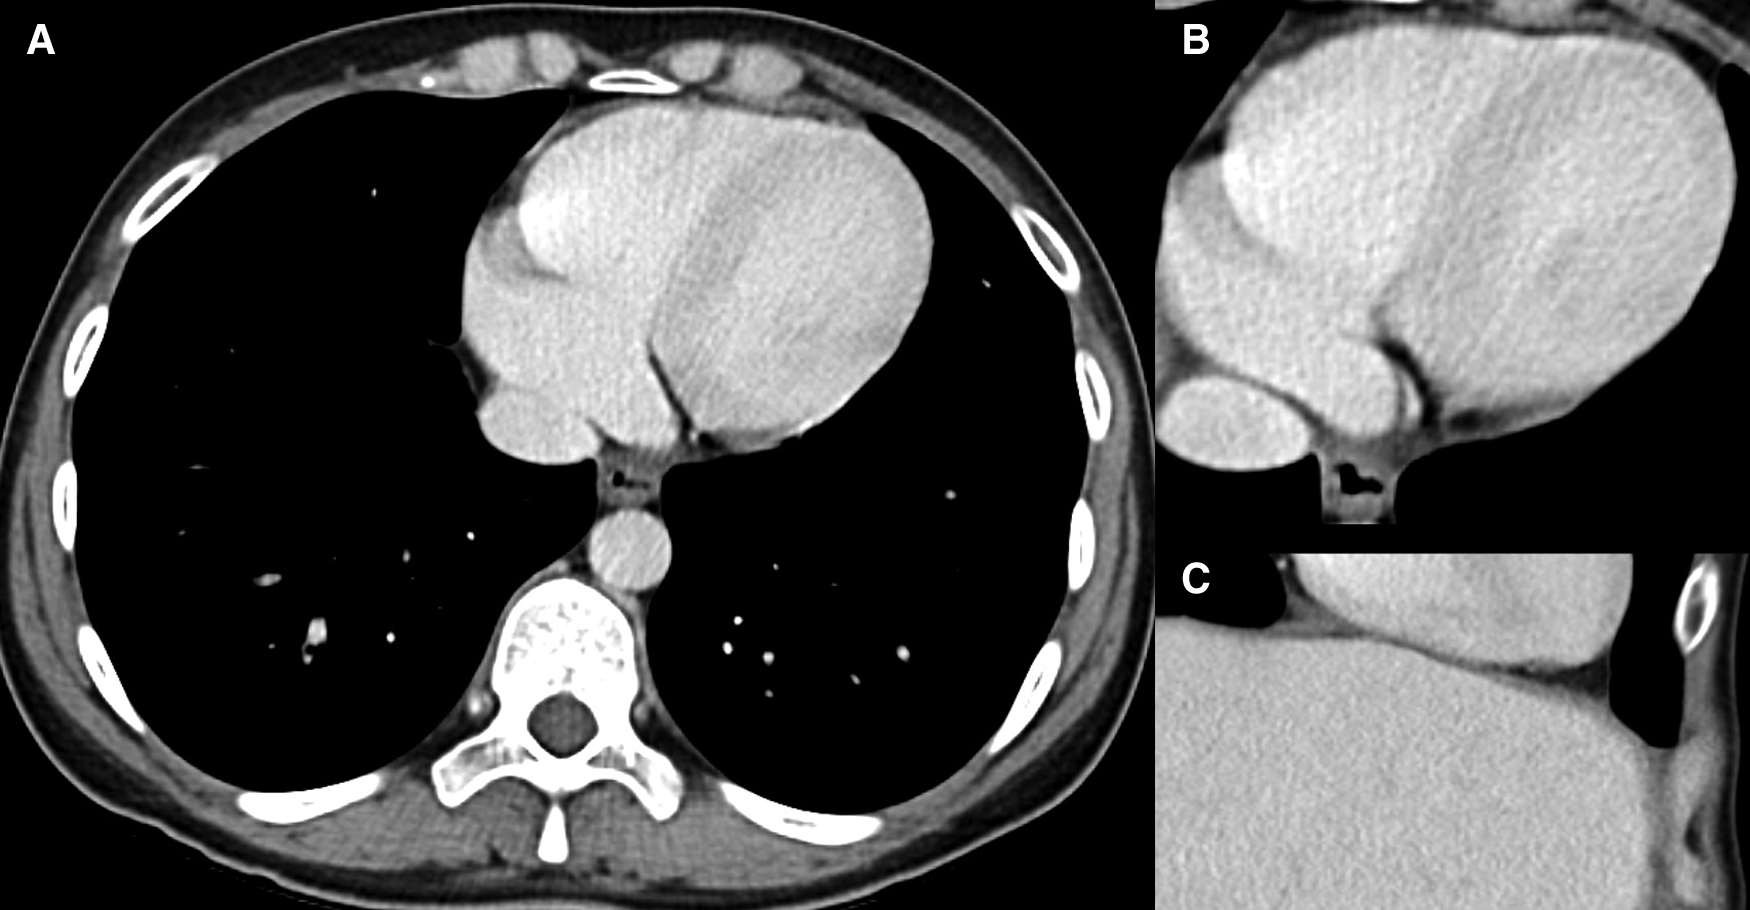

Figure 2

Normal cardiac contrast enhancement. 40-year-old male patient who underwent CE MDCT of the abdomen in (A,B) axial orientation and (C) coronal section. Note the homogeneous contrast of the myocardium, as far as covered.